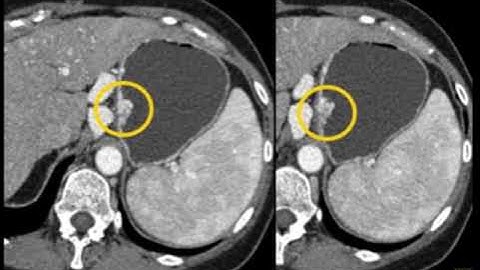

Gastric GIST Tumors: Pearls and Pitfalls - Part 1